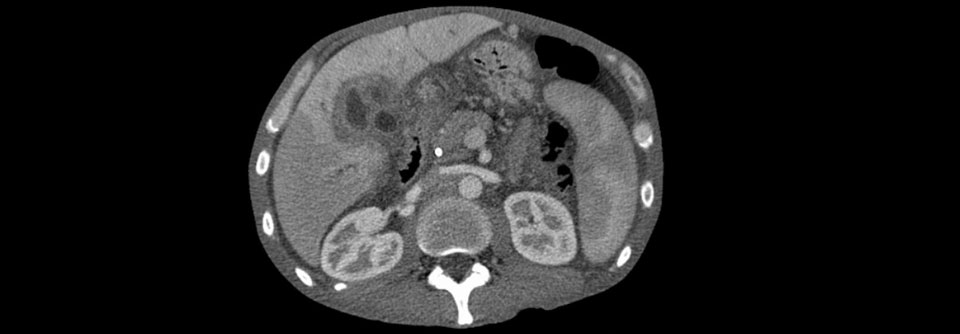

Jedes Jahr entwickeln 2–3 von 100 000 Menschen Gallengangskrebs, Tendenz steigend. Jedes Jahr entwickeln 2–3 von 100 000 Menschen Gallengangskrebs, Tendenz steigend. © Science Photo Library/FREEMAN HOSPITAL, NEWCASTLE/SIMON FRASER